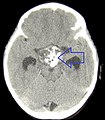

Imaging

Radiology:[1]

- Calcifications (adamantinous type).

- Contrast enhancing.

- Cystic portions.